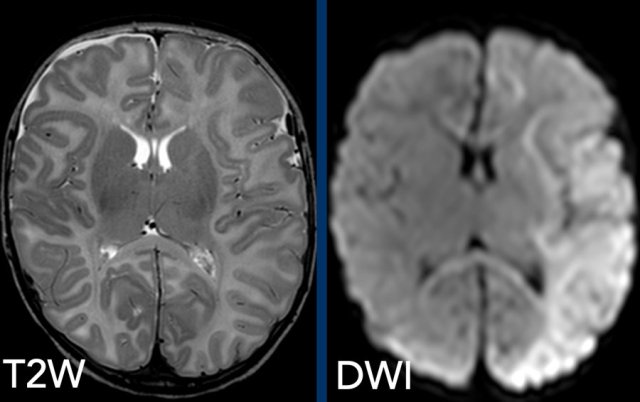

Perfusion defects are a major component of long

Therefore diffusion weighted imaging (DWI) should also be part of the

standard MR imaging protocol.

Images

2-month-old boy with metaphyseal avulsion fractures, rib fractures and

convulsions. T2-weighted image shows subtle right frontal subdural fluid

collection, but massive diffusion restriction on DWI.